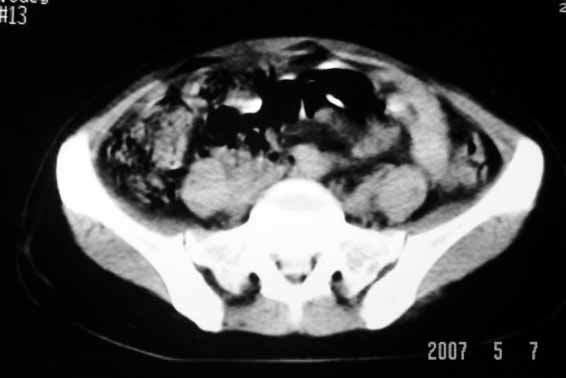

标题: CT8123:女46岁,左下腹胀痛不适1月,以前曾有月经过多史,现已 [打印本页]

标题: CT8123:女46岁,左下腹胀痛不适1月,以前曾有月经过多史,现已

考虑子宫肌瘤(变性)或子宫腺肌病,不排除内膜ca可能,不增强建议结合mri或b超检查。

子宫们内膜癌或子宫颈癌体部浸润并右侧腹股沟淋巴结转移

考虑子宫肌瘤,不排除子宫内膜ca可能,不增强建议结合b超检查。